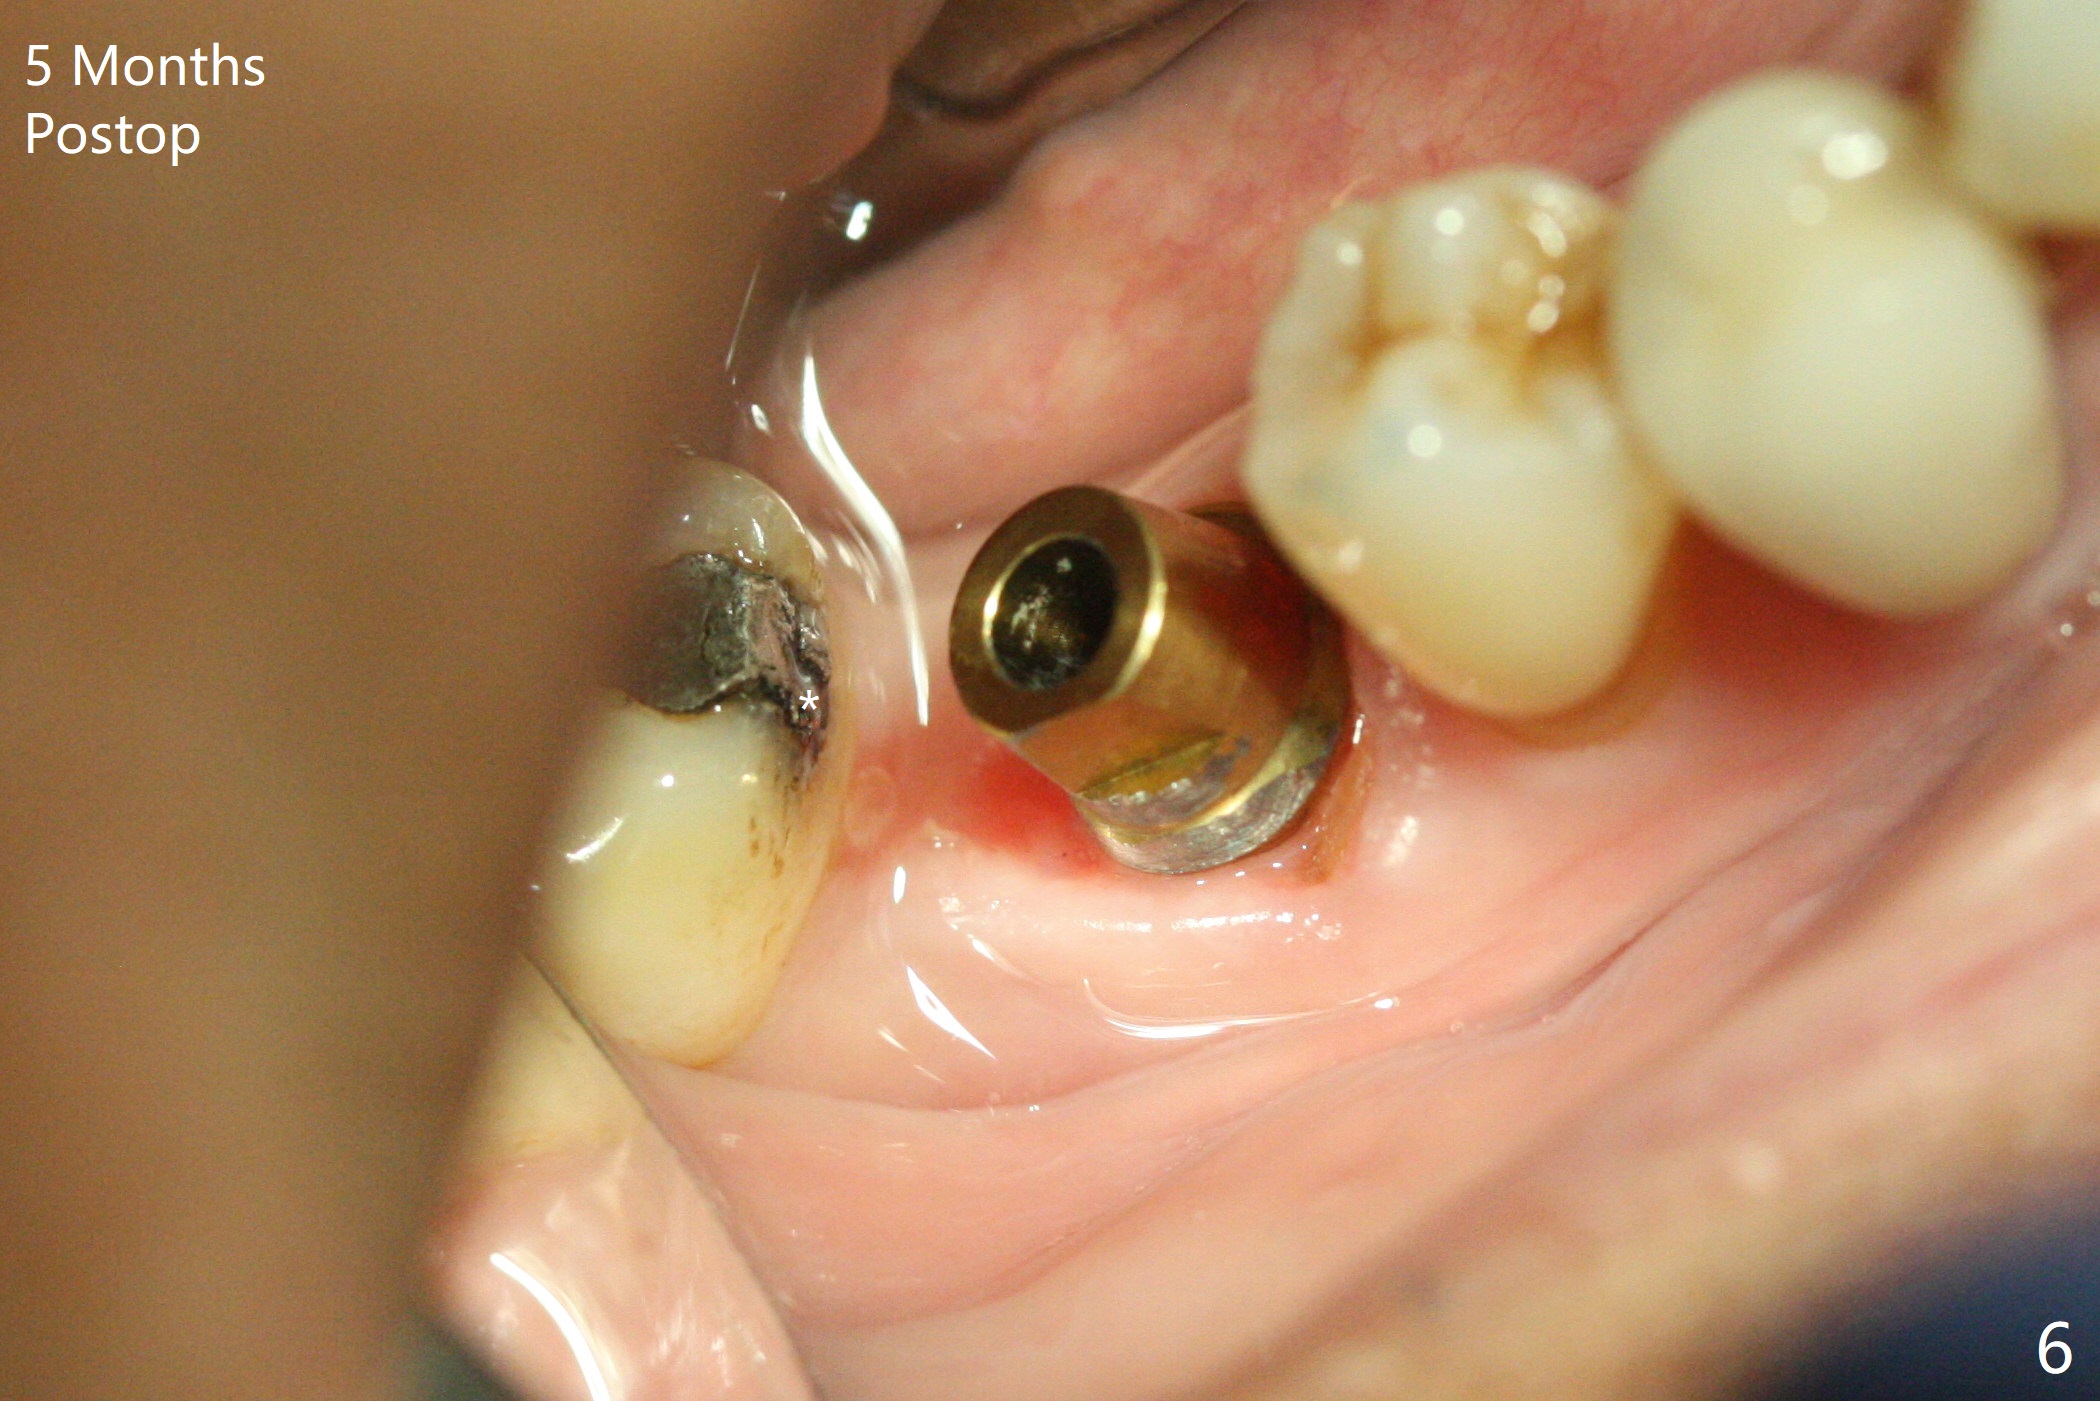

In spite of severe bone loss and 1.86 mm remaining bone after extraction of the tooth #30, a 5x7.3 mm implant achieves insertion torque of 35 Ncm with an immediate provisional (Fig.1). Periodontal dressing is applied for additional fixation of the bone graft (*) and Osteogen plug (P). Although the implant is placed in the mesial socket, the coronal end of the abutment is in the middle of the edentulous area. The patient is extremely pleased with no pain surgery. There is no postop paresthesia. The periodontal dressing (Fig.2 D) remains in place and buccal to the temporary crown (T) 10 days postop. When the former is removed, there is a gap between the margin of the provisional and that of the gingiva (Fig.3 between arrow and arrowhead), suggesting that the latter has shrunk postop. If there were no periodontal dressing, some of bone graft may have been lost. The distal socket heals when the immediate provisional is removed for revision 5 weeks postop (Fig.4). With gingival retraction cords, the abutment margin is prepared 2 months postop, particularly distal, to reduce food impaction in the future. If there is no abutment screw loosening with final restoration, it suggests that computer designed trajectory is acceptable. The implant plateau seems to be covered by the bone 4.5 months postop (Fig.5). In fact the mesiobuccal margin of the abutment is close to the corresponding crestal bone. The gingiva looks healthy 5 months postop (immediately before cementation, Fig.6), although MO amalgam of the tooth #31 is breaking down (*). Return to Lower Molar Immediate Implant, Prevent Molar Periimplantitis (Protocols, Table), Trajectory Xin Wei, DDS, PhD, MS 1st edition 04/17/2019, last revision 09/14/2019